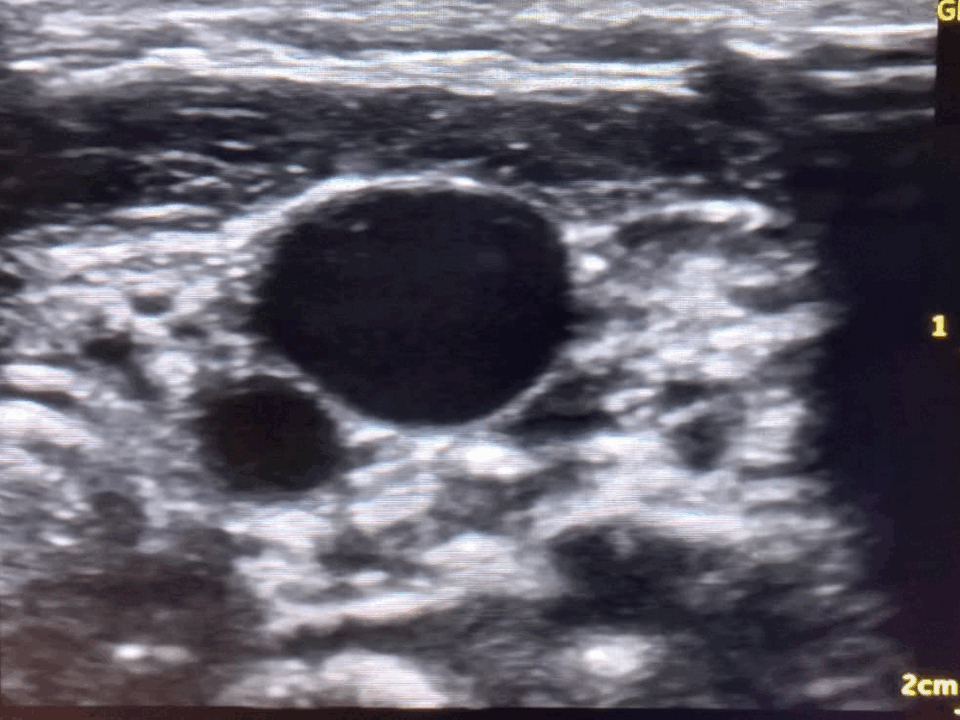

Using a simple, low-cost phantom line model made from chicken and balloon, we taught trainees the fundamentals of ultrasound-guided vascular access before progressing to supervised practice.

We begin with ultrasound basics, including vessel identification, probe handling, and needleโprobe coordination, before moving on to essential techniques such as Dynamic Needle Tip Positioning (DNTP) and the Vanishing target sign.